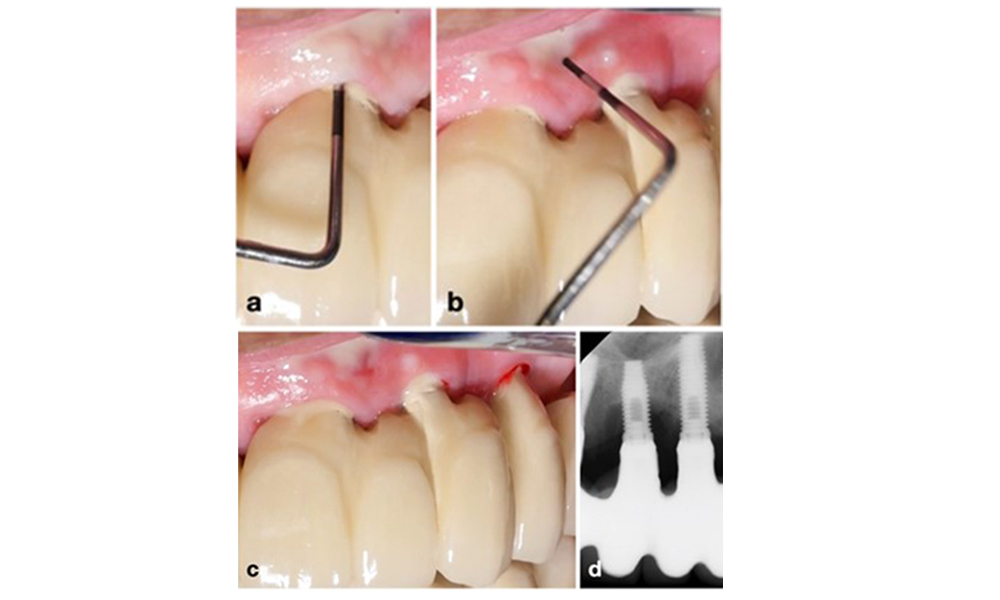

To achieve consistent and comparable radiographs over time without overlapping implant-threads, a simple mnemonic rule can be followed: “right blur, raise beam & left blur, lower beam – RBRB/LBLB” (see figure 3 adapted from Schropp et al. 2012).

For optimal intraoral radiographs of dental implants, follow this mnemonic rule: If the right side of the implant appears blurry on the peri-apical x-ray, raise the beam (i.e., directed more towards the ceiling) (a); if the left side appears blurry, lower the beam (i.e., directed more towards the floor) (b). This rule applies regardless of implant position in the upper or lower jaw. Example: Blurry threads on implants at positions 14 and 16, mostly at their right side, (c) were corrected by raising the beam by about 15 degree, resulting in a clear image showing bone-to-implant contact (d).

Figure 3. For optimal intraoral radiographs of dental implants, follow this mnemonic rule: If the right side of the implant appears blurry on the peri-apical x-ray, raise the beam (i.e., directed more towards the ceiling) (a); if the left side appears blurry, lower the beam (i.e., directed more towards the floor) (b). This rule applies regardless of implant position in the upper or lower jaw. Example: Blurry threads on implants at positions 14 and 16, mostly at their right side, (c) were corrected by raising the beam by about 15 degree, resulting in a clear image showing bone-to-implant contact (d).